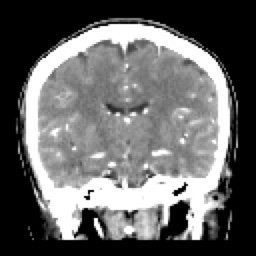

SIMPLE FINO COR (8) 91 images

ARTERIAL FINO COR (10) 90 images